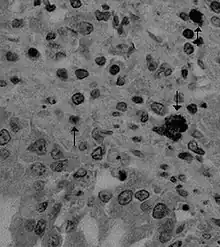

| Canine coronavirus antigen (arrows) in canine lung tissue | |